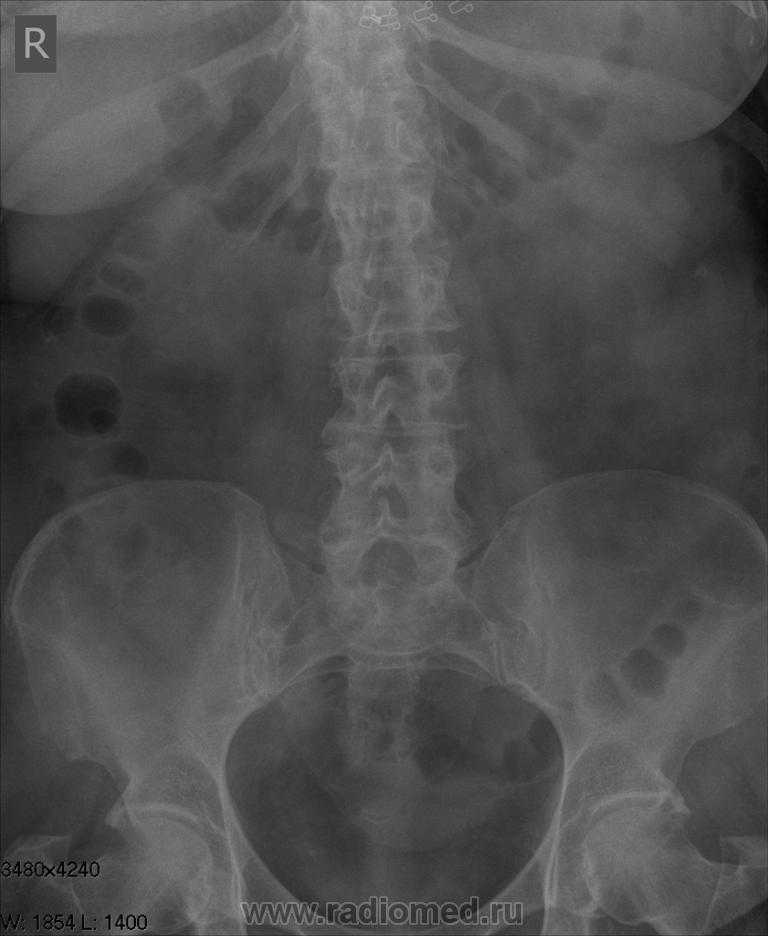

Экскреторная урография при нефроптозе: диагностические изображения